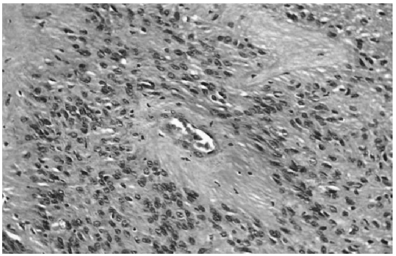

Com base na imagem acima, o diagnóstico mais provável é o de